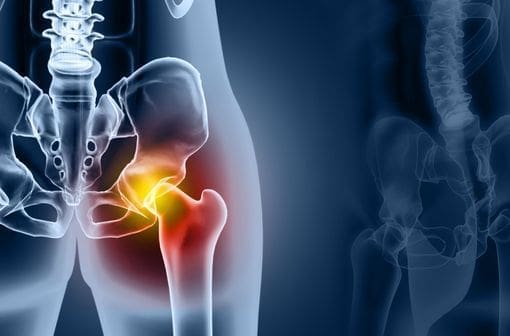

La douleur à la hanche droite est une inconfort qui peut rapidement devenir un véritable casse-tête. Identifiée par des sensations variées comme des tiraillements ou une raideur, elle mérite une attention particulière. Comprendre sa signification et ses causes permettra d’y remédier efficacement.

Lorsque la douleur se manifeste au niveau de la hanche droite, plusieurs facteurs peuvent être en jeu. Cela peut aller d’une simple tension musculaire à des affections plus sérieuses. La localisation et l’intensité de la douleur sont des éléments clés pour cerner son origine.

La région de la hanche est un carrefour important pour de nombreux muscles, tendons et ligaments. Les douleurs peuvent être causées par :

• Tendinite : Inflammation des tendons qui se traduit par une douleur accrue lors des mouvements.

• Bursite trochantérienne : Inflammation des bourses séreuses, souvent liée à des mouvements répétitifs.

• Arthrose : Usure progressive du cartilage articulaire, causant raideur et douleurs persistantes.